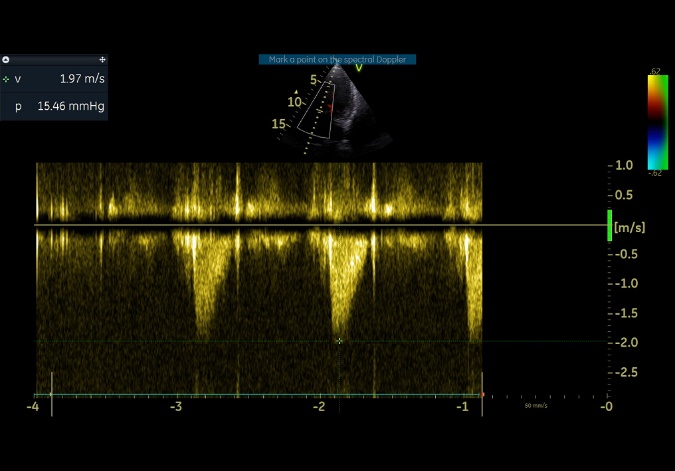

术后即刻评估

术后平均压差在10mmHg以内,几乎无反流,瓣膜正常工作。